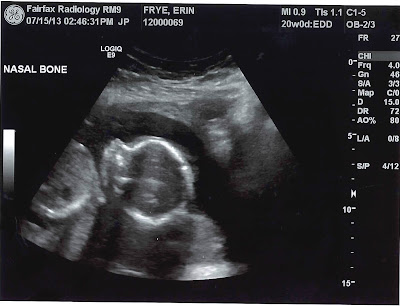

Well, if you haven't heard already, we found out on Monday that we're having a little baby BOY! Billy and I are so excited and can't wait to meet the little guy. It was a long process on Monday trying to reveal the gender. My ultrasounds are performed at an ultrasound facility next door to my OB's office. The technician spent over an hour and a half with me and my tummy (with Billy in the room) trying to check out all of Fryebaby's parts and pieces...which was no easy task. Turns out we have a modest one who is already anti-paparazzi. His arms and hands were waving in front of his face the entire time, and his legs were crossed and pulled in tightly. Little by little, the technician was finally able to see his nose, lips, brain, all four chambers of the heart, his spine, the umbilical cord, and last, but not least, his private region. All checked-out and he appears to be a healthy little dude. She estimated that he is 12 ounces and had a healthy heart rate in the 130s. Here's a photo of his precious little nose and head.

If the photo is not clear enough, or you can't imagine how big a 12 oz. baby is, my BabyBump app says he's the size of a small cantaloupe this week, about 6-1/2 inches long.